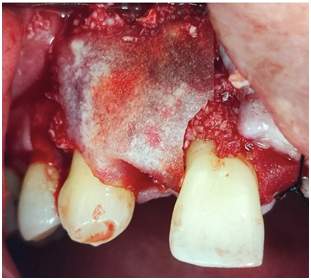

A 22-yer-old female patient required extraction of the upper right central incisor finding a type III socket by this it is used particulate cortical bone graft and resorbable membrane without place the implant in this phase (Figure 7.A and Figure 7.B).

A male patient in sixth decade of life who presented a type III socket with a dehiscence <75% with thin biotype by this reason it is decided to bone regeneration with puros, cortico-cancellous bone and membrane (Figure 10).